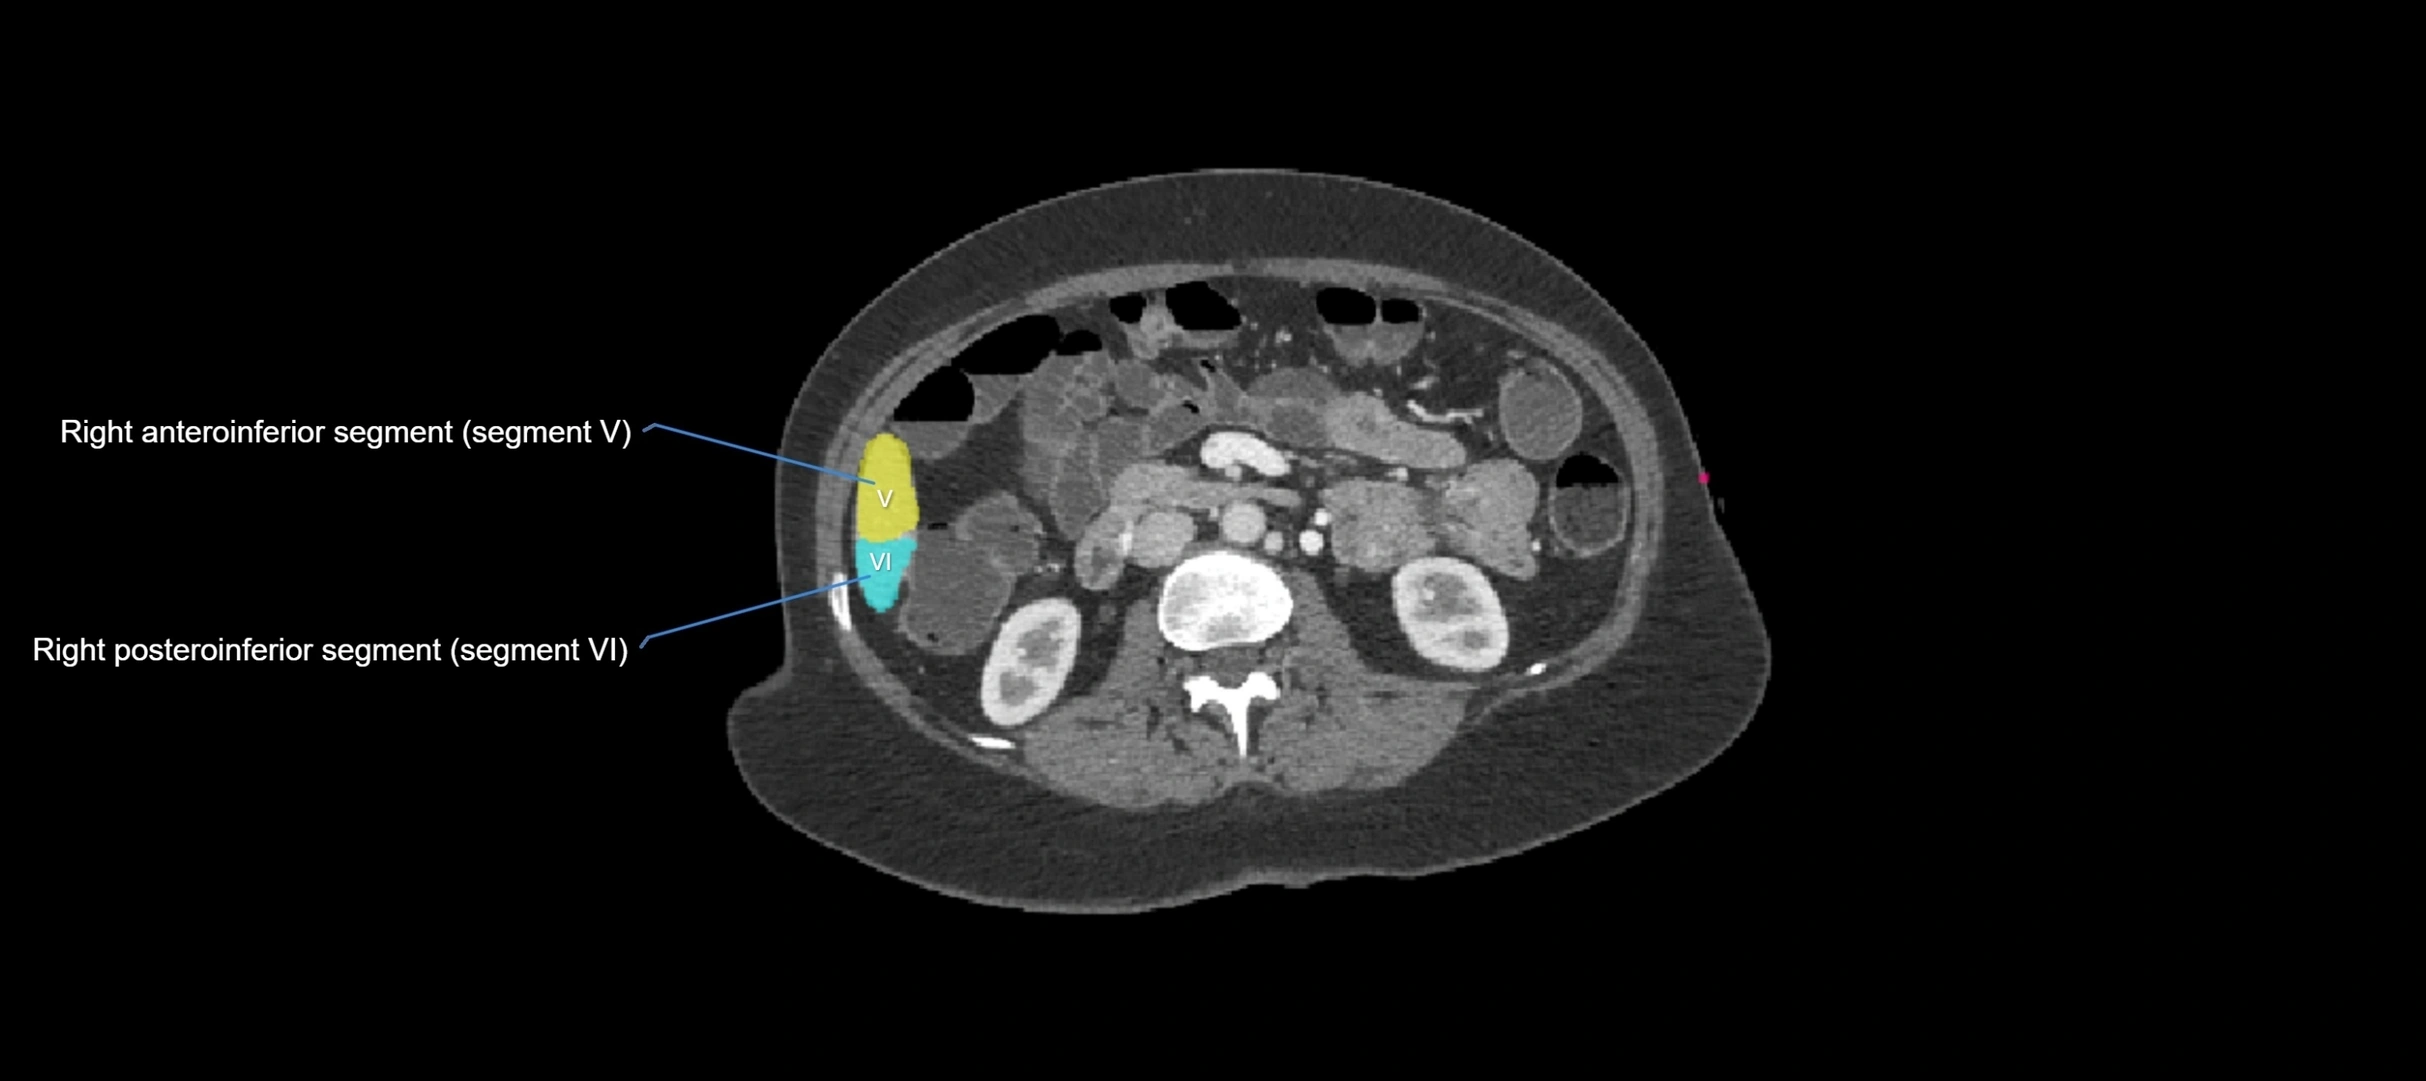

CT Image

image